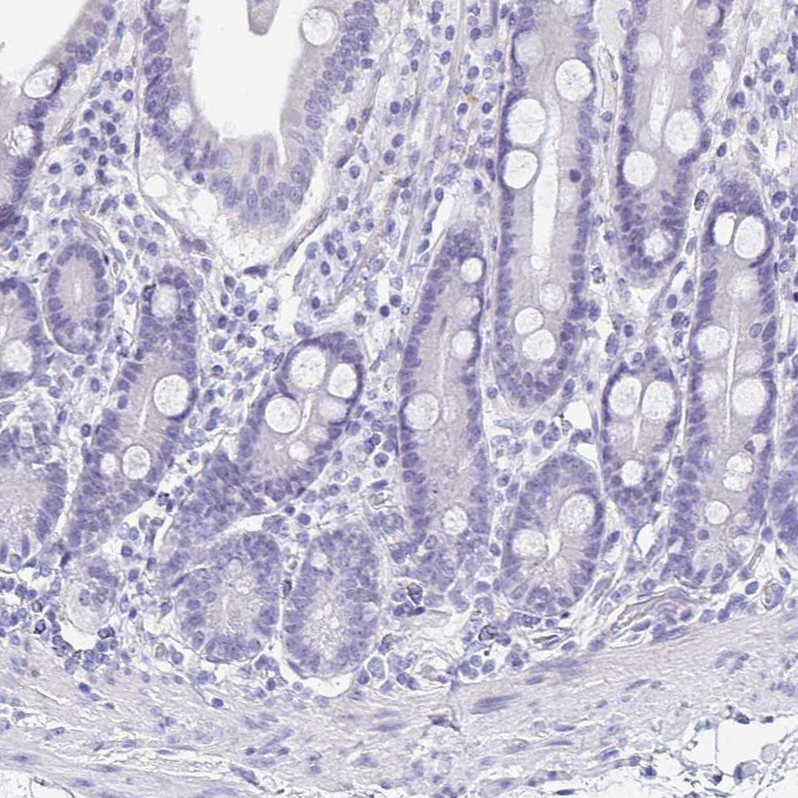

Immunohistochemistry analysis in human esophagus and liver tissues using HPA051062 antibody. Corresponding TMPRSS11E RNA-seq data are presented for the same tissues.